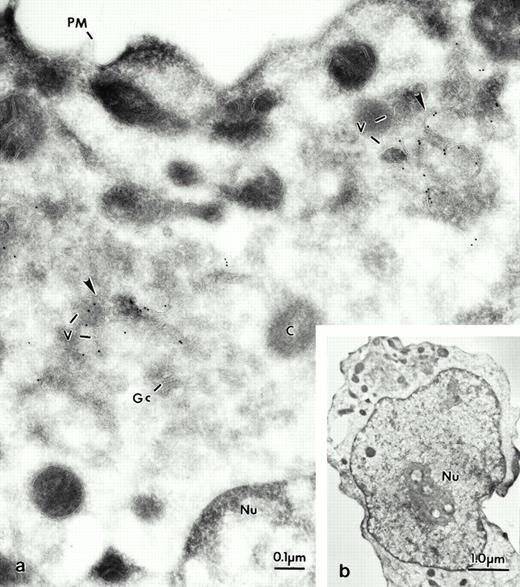

Electron micrograph of a frozen thin section of an immature neutrophil labeled for LAMP-2, using the MoAb H4B4. At lower magnification the cell can be identified as a promyelocyte (see b). The Golgi region of this cell can be seen at higher magnification in a. Most of the gold grains are present in vesicular structures (arrows). The vesicles (v) are concentrated near the Golgi complex (Gc) and the centriole (C). Note the absence of label on the plasma membrane (PM). Nucleus (Nu).